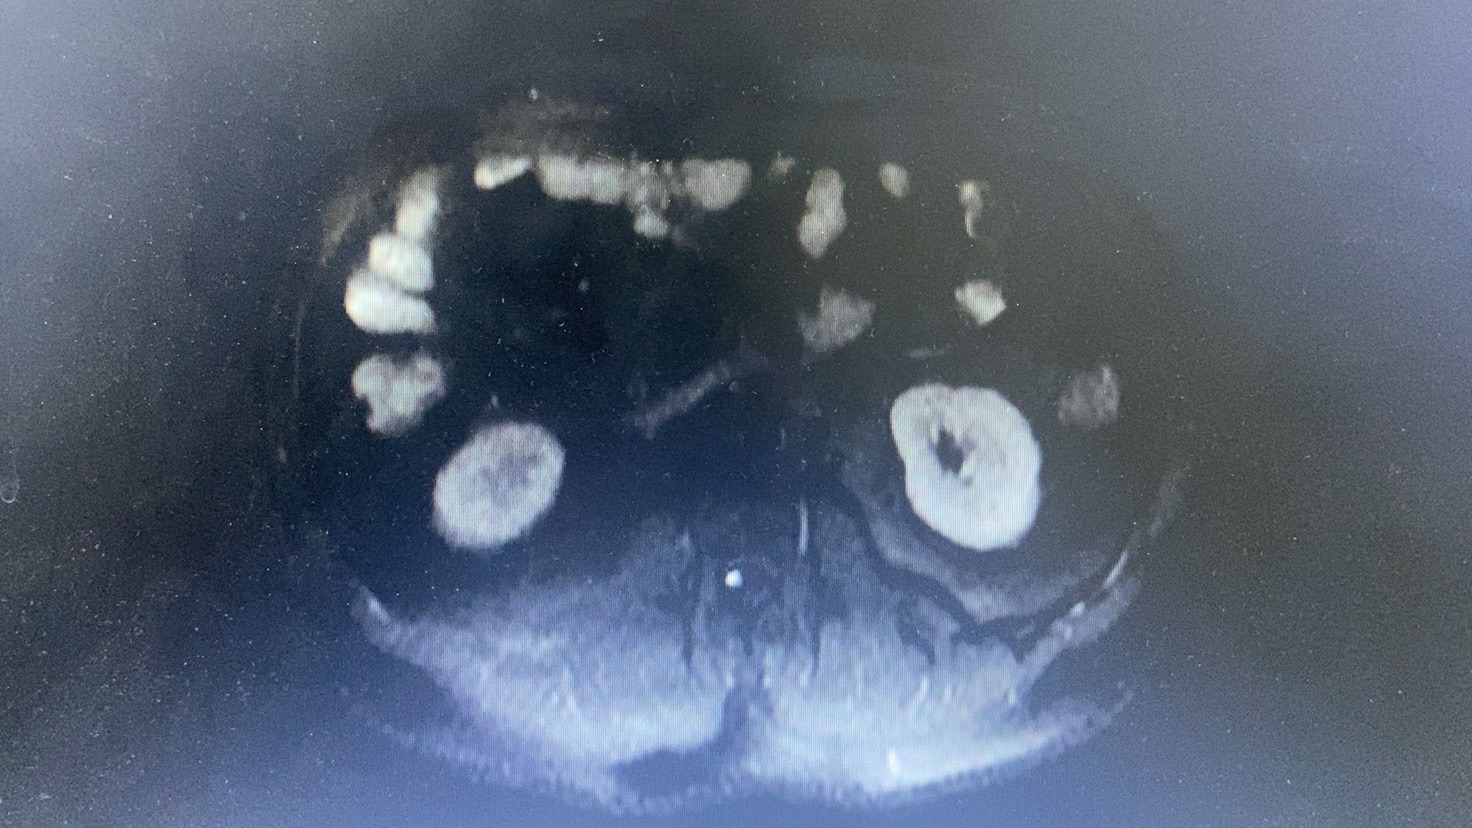

腹部核磁: